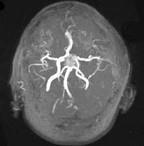

问题 男性,55岁,头痛一年余,两个小时前突然出现剧烈头痛,MRI检查如图所示,最可能的诊断为()

选项 A.垂体瘤 B.脑膜瘤 C.颅咽管瘤 D.垂体瘤并卒中 E.动脉瘤

答案 D